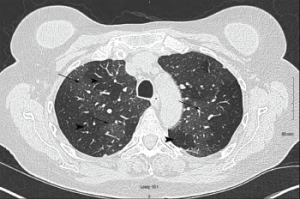

Figure 2a: Transverse Section

Arrowheads indicate areas of hyperlucency, suggesting air trapping, compared with hypolucent areas, indicated by arrows.

Chest radiography typically reveals clear lungs, often with hyperinflation, but HRCT of the chest is the diagnostic imaging modality of choice. Classic HRCT findings of OB-RA are mosaic attenuation and hyperinflation. Mosaic attenuation is defined as patchy areas of hyperlucency due to air trapping from bronchiolar obstruction and is best recognized during expiration (e.g., dynamic phase HRCT). Other common HRCT findings are bronchial wall thickening, cylindrical bronchiectasis and centrilobular pulmonary nodules.12